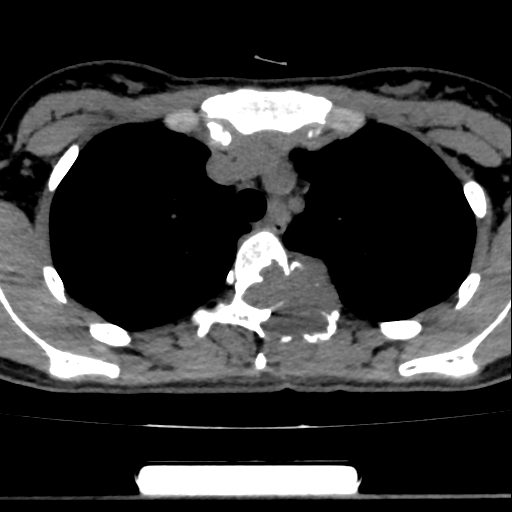

经过详细的影像学检查,一个令人不安的发现浮出水面:她的第4胸椎(T4)出现了明显的骨质破坏。为进一步明确诊断,小林随后前医院进行了相关检查。结果证实,她的T4椎体左旁长有一个神经源性肿瘤,这个肿瘤已经侵蚀了T4椎体及附件,并累及了相邻的左侧第4根肋骨。

神经源性肿瘤虽多为良性,但其生长位置极其“刁钻”,紧邻脊髓、主动脉、心脏等重要结构,且血供往往非常丰富。根治的唯一方法是手术切除,并进行椎体重建术以稳定脊柱。然而,这颗被喻为“埋在生命交通枢纽旁的炸弹”,使得手术难度和风险呈几何级数攀升。

“这个区域血管网络错综复杂,肿瘤本身血供丰富,术中一旦大出血,止血将极为困难,视野会被淹没,不仅肿瘤难以切净,更可能损伤脊髓导致瘫痪,甚至危及生命。”骨科专家坦言,此类手术常规预期出血量可达3000毫升以上,相当于一个成年人全身血液总量的三分之二,术中大量输血和相关并发症风险极高。